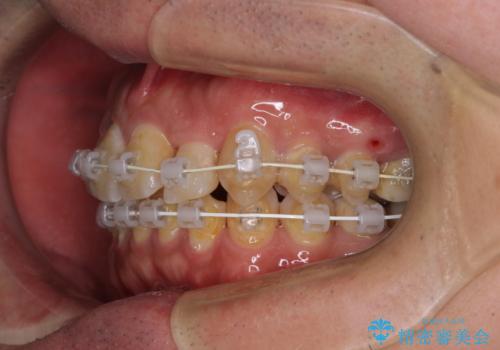

虫歯治療途中の歯は仮歯が装着されていたため、そのまま矯正治療を行い、矯正後に補綴治療を行うこととしました。

インビザライン矯正では苦手とする舌側転位した前歯をスムーズに改善することができました。